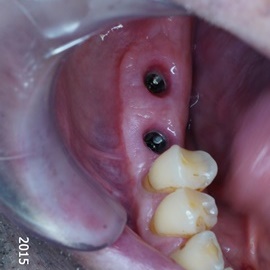

Pacjentka głosiła sie do naszego gabinetu do leczenia z osadzonym mikroimplantem w pozycji lewej dolnej dwójki. Siostrzany implant w pozycji prawej dolnej dwójki wypadł wcześniej, około 1,5 roku od implantacji. Odtworzono przedsionek i dziąsło rogowaciejące, osadzono dwa implanty, jednoczasowo z regeneracją kości. Dopiero na etapie ostatecznej rekonstrukcji protetycznej usunięto zachowany mikroimplant. To się nazywa motywacja do leczenia! Pacjentka przygotowywała sie na ślub prawnuczki :)